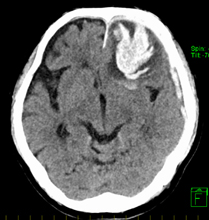

急性硬膜下血種

血腫が硬膜と脳の間に生じるもので、大脳表面の血管や架橋静脈(硬膜と脳の間を走る静脈)の損傷で出血がおこります。脳挫傷を合併していることも少なくありません。外傷性頭蓋内出血の中に占める割合は最も大きく、その多くは頭蓋骨骨折を伴わず外力の反対側に生じます。

症状としてみられるのは、頭部外傷の直後からの意識障害や、けいれん・片麻痺などで、基本的には手術によって血腫を除去します。術後もICUにて神経集中治療を要することが多く、予後(経過)は概してよくありません。